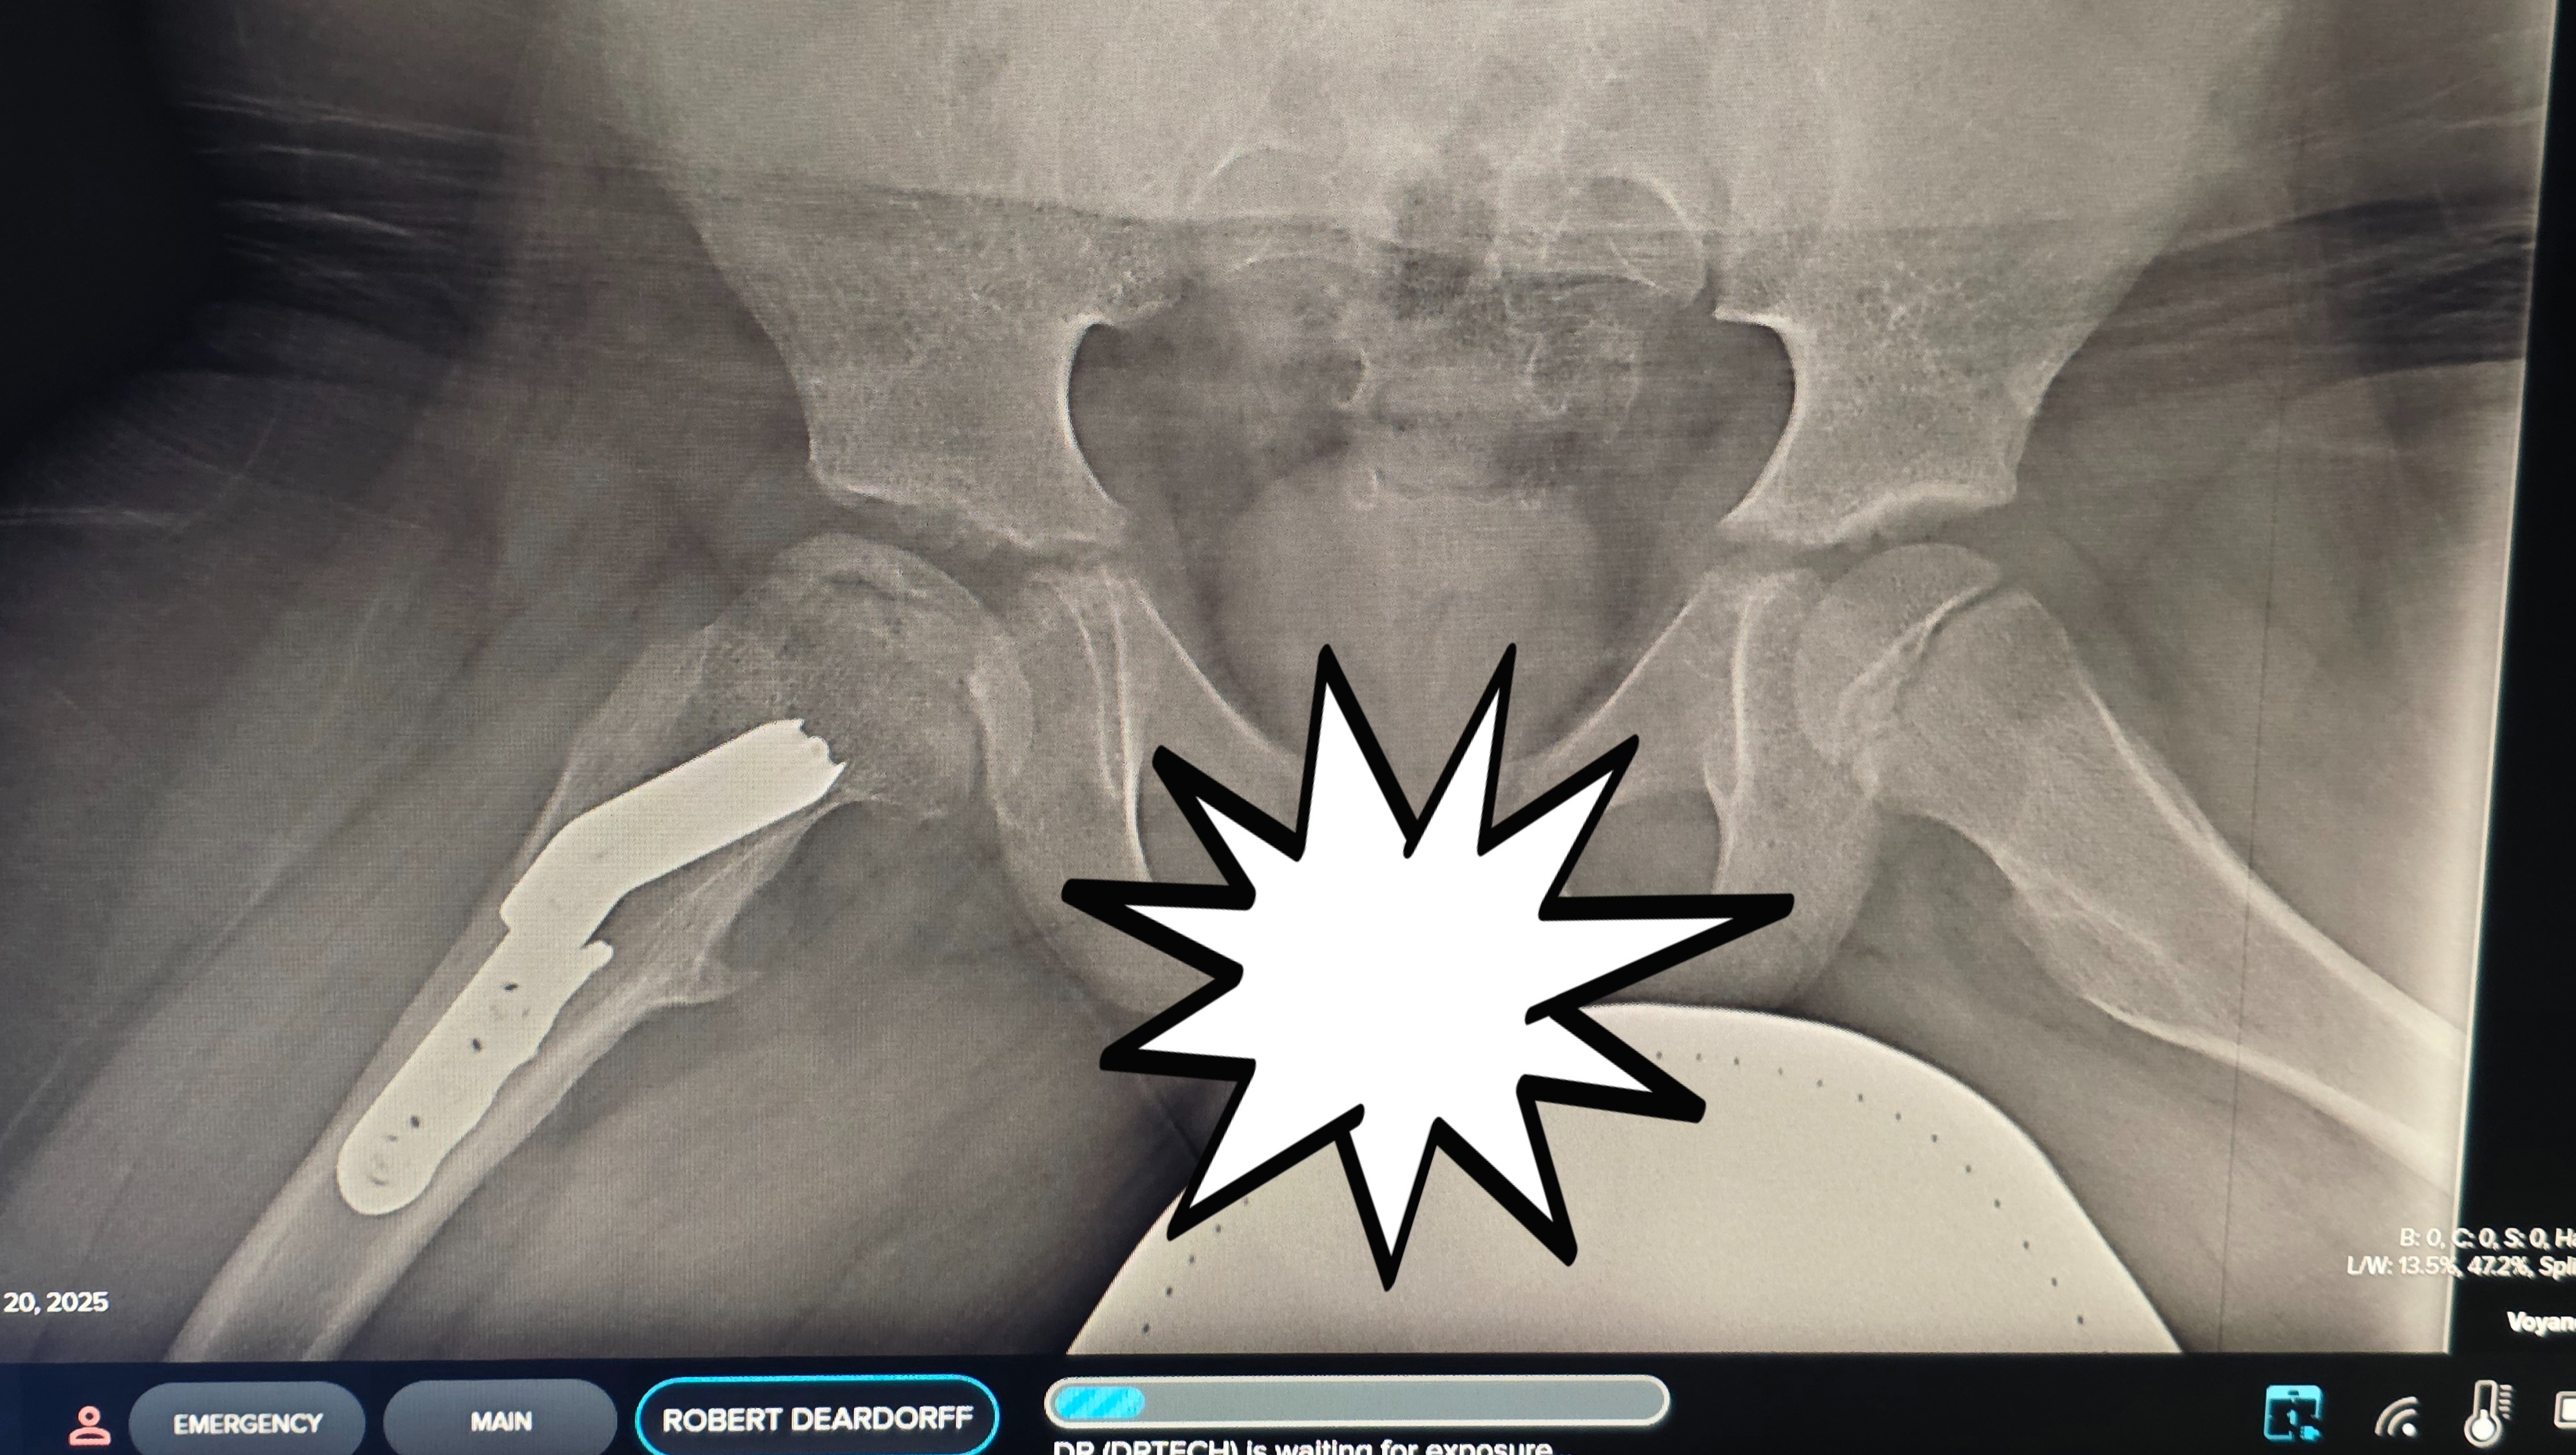

Unfortunately, follow-up x-rays in February of 2025 showed that Robbie’s hip was beginning to fragment and lose containment.

X-ray taken February 20th, 2025.